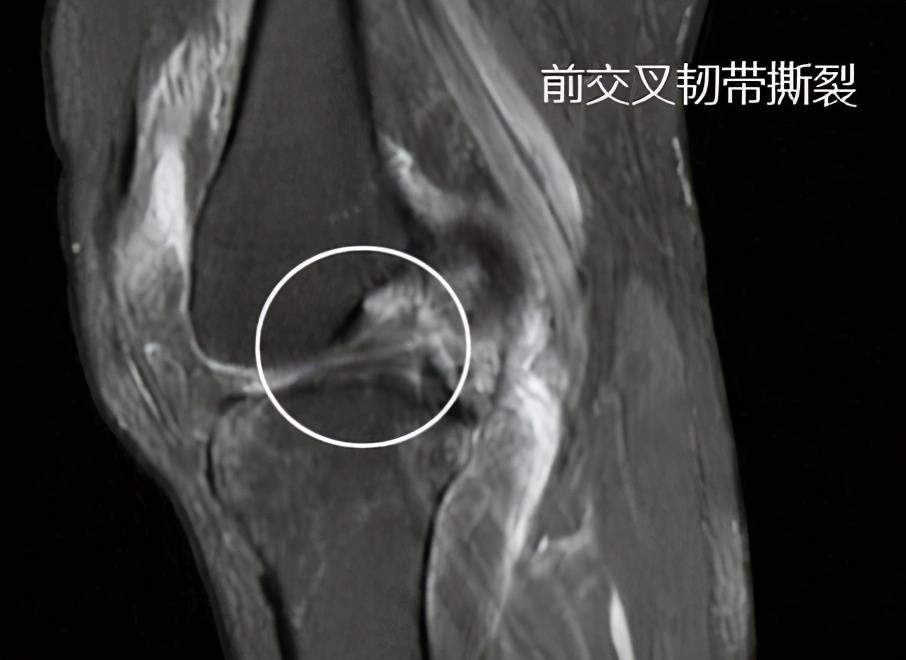

核磁共振韧带断裂图

膝关节韧带图片断裂